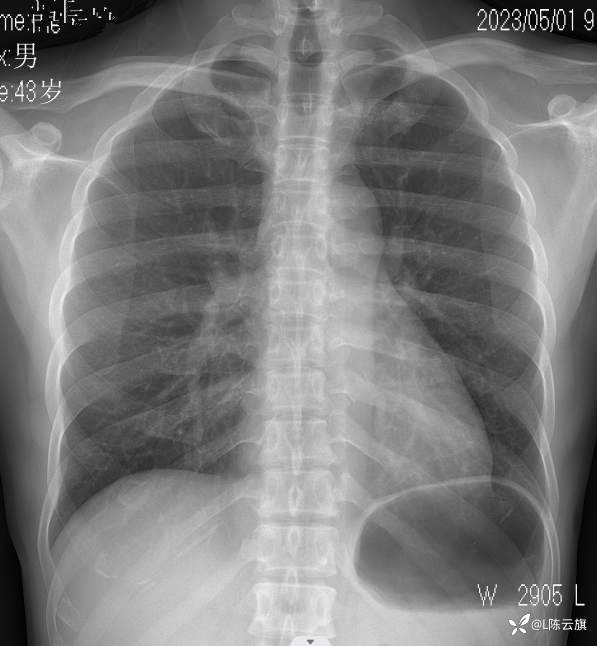

【2403胸部影像病例】 胸部平片你看到的这是什么基本病变?

1、患者男,44岁,精神长期住院患者。近一年反复发热、咳嗽、咳痰,无其他症状。每次进行胸片检查发现肺部炎时,经治疗后病灶吸收,不久又复发。

2、是否可以试述一下病变在哪里?是什么基本病变吗?

胸片1: